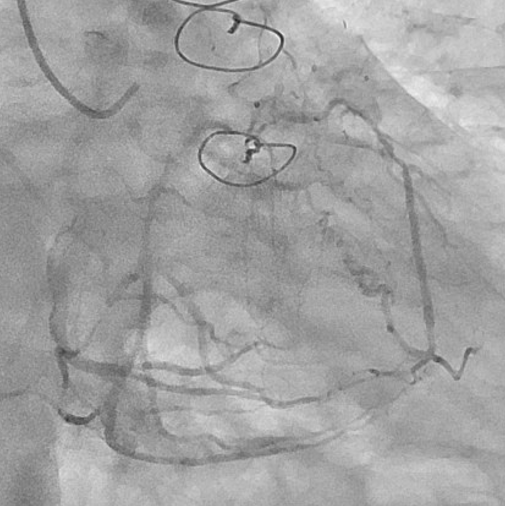

The left internal thoracic artery–left anterior descending artery (LAD) graft was completely occluded, and the native left coronary artery (LCA) was also occluded at the ostium of the left main trunk (LMT). The right coronary artery demonstrated no significant stenosis. From a right ventricular branch, non-interventional epicardial channels opacified the separated LAD and left circumflex artery. The occlusion length from the ostium of the long LMT to the bifurcation, was approximately 15 mm.

First, percutaneous coronary intervention (PCI) was performed toward the left anterior descending artery (LAD). The initial antegrade wire deviated from the true lumen; therefore, parallel wire technique was employed to achieve successful crossing. To avoid jailing the left circumflex artery (LCX) ostium, the stent was deployed precisely at the LAD ostium, and the left main trunk (LMT) was dilated using a 4.0-mm cutting balloon. One month later, intervention toward the LCX was undertaken. Intravascular ultrasound (IVUS) performed from the LAD confirmed achronic total occlusion (CTO) entry with a markedly thick plaque covering the LCX ostium. Although the lesion was accurately marked, penetration with a high-penetration guidewire was unsuccessful. Even with the balloon screen technique using a CP 8-20, wire penetration remained unsuccessful. Therefore, plaque debulking was selected to expose the CTO entry. Directional coronary atherectomy (DCA) was performed, and follow-up IVUS demonstrated significant plaquethinning compared with baseline. Subsequently, the CP 8-20 wire advanced smoothly, enabling successful wire crossing. The procedure was completed usinga mini-crush stenting strategy.